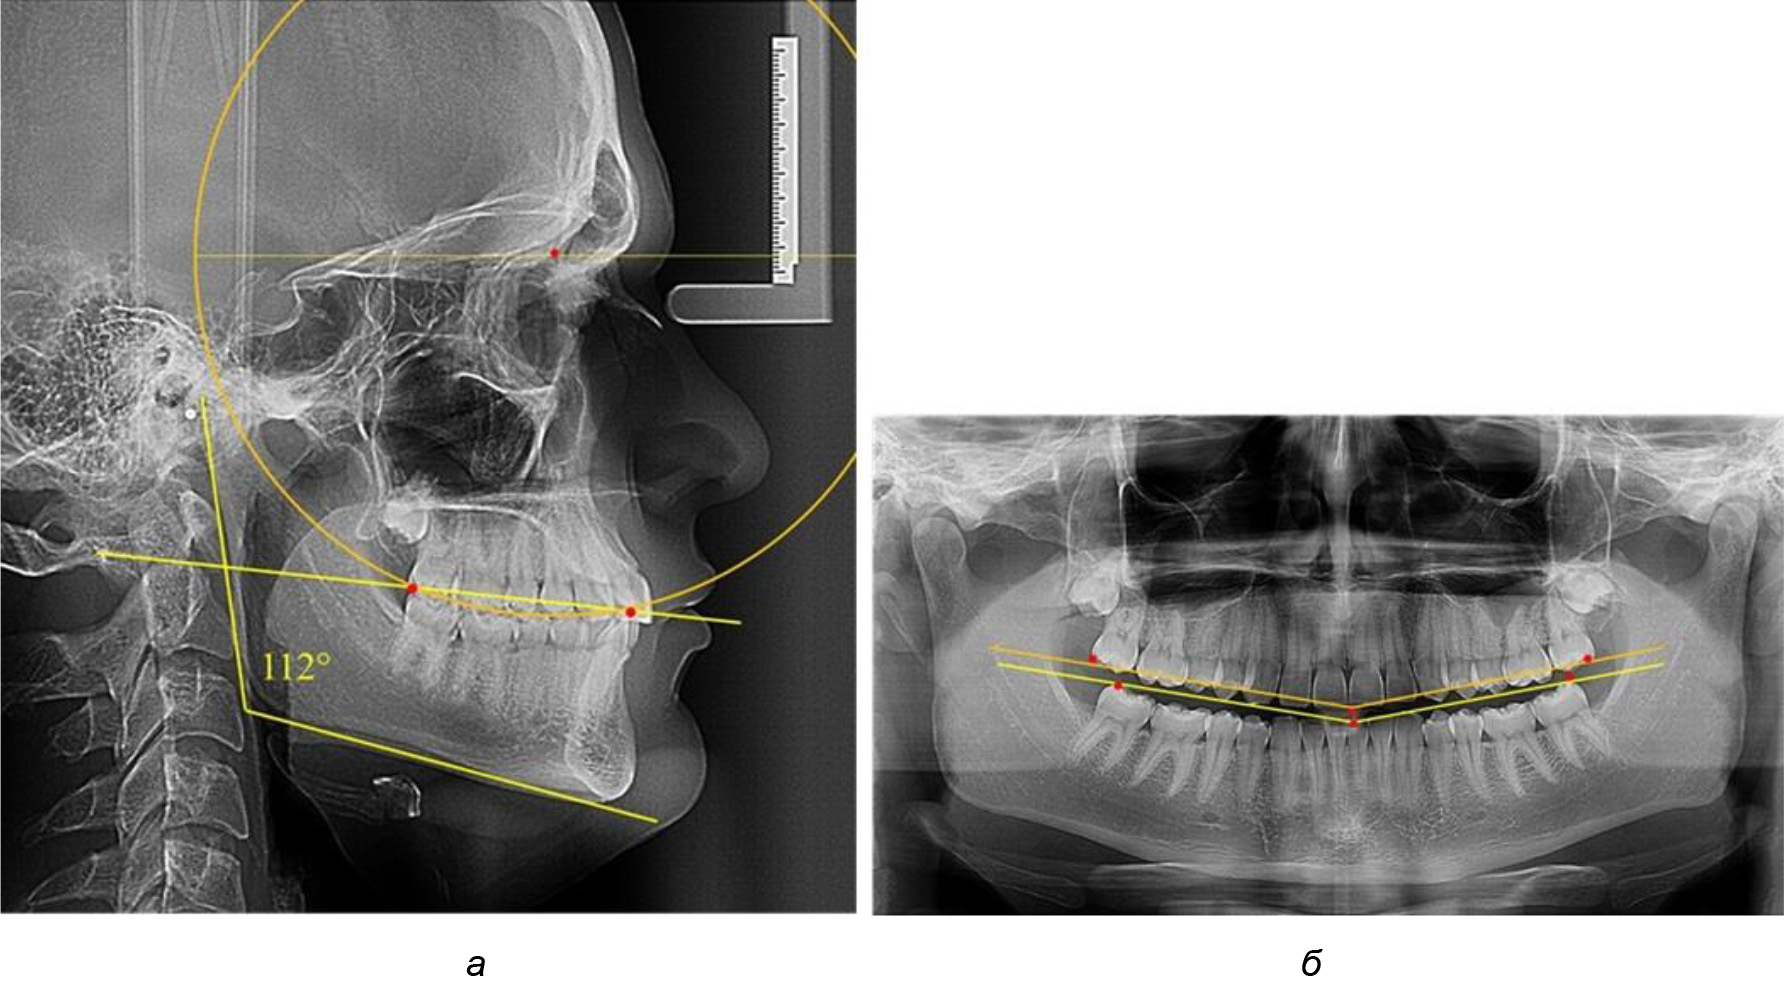

У людей с аномалиями окклюзии по сагиттали в 1-й подгруппе обследовано 9 человек. Обращает на себя внимание увеличение глубины кривой Spee, что нами расценивалось, как патологическая форма кривой линии окклюзии.

Глубина кривой Spee в среднем по 2-й подгруппе составила (5,69 ± 1,57) мм, что было достоверно больше, чем у людей с физиологической окклюзией (р ˂ 0,05). Достоверных различий с показателями, полученными при анализе ТРГ и ОПТГ, нами не отмечено (р ˃ 0,05). Отношение радиуса окружности к сагиттальному размеру окклюзионной линии в среднем по подгруппе составляло 1,372 ± 0,042 и не соответствовало числу Фибоначчи, что может быть использовано в качестве диагностического критерия определения патологической формы кривой Spee. После лечения пациентов техникой «прямой» дуги было отмечено незначительное увеличение сагиттального размера окклюзионной лини в среднем на (2,12 ± 0,77) мм. Однако окклюзионная линия практически касалась окклюзионного контура всех жевательных зубов, и отмечалось практически полное отсутствие кривой Spee.

Таким образом, проведенное лечение техникой «прямой» дуги способствует нормализации окклюзионного равновесия и торку передних зубов, однако не соответствует оптимальному окклюзионному статусу, характеризующему физиологическую окклюзию. При этом величина нижнечелюстного угла оставалась на прежнем уровне (рис. 5).

Рис. 5. Особенности ТРГ при патологической кривой Spee до лечения (а) и после лечения (б) техникой «прямой» дуги